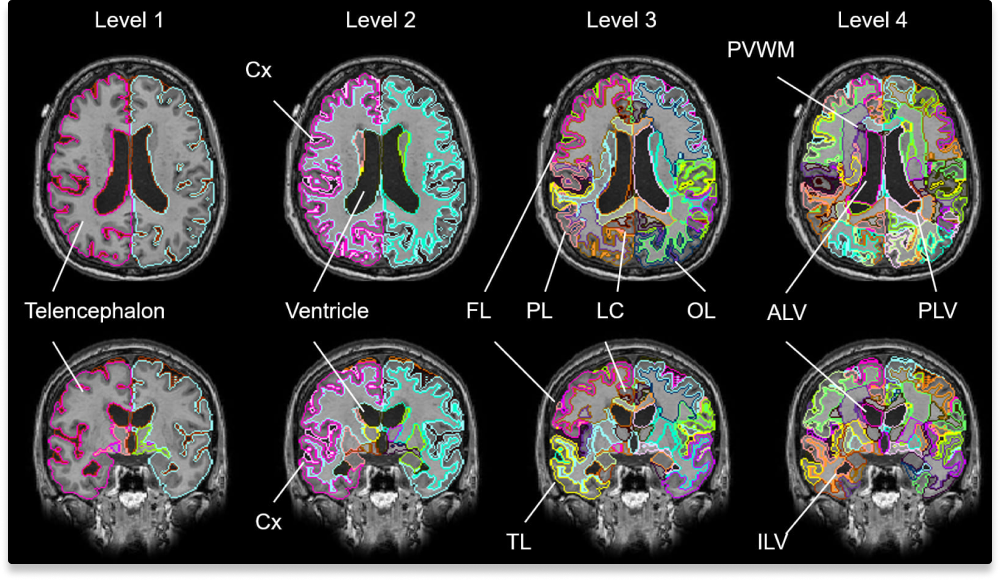

AIが認知症リスク因子を定量化

認知機能低下の要因となる脳萎縮や白質病変、全脳505構造を解析。人間の目では評価が難しい微細な変化も定量化します。